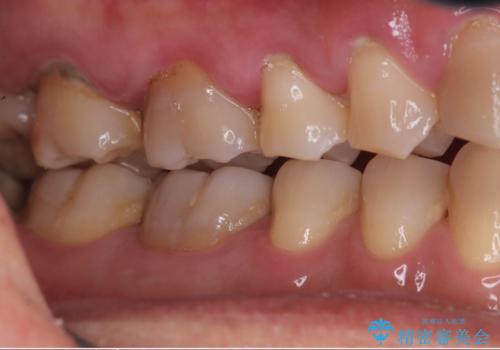

- 学生の頃、前歯をぶつけ歯科を受診したがまだ成長期のため、積極的治療は避けようと言われ十年以上歯科にかかっていなかった患者様です。

前歯は触れると抜けそうで全体的には歯肉の腫れも著しく歯石が沢山ついている状態でした。

歯肉の中にも歯石がついていため細かいスケーリングを何回かに分けて行い、日々の歯磨きのポイントを伝えた所、歯肉の出血や腫れも良くなり、前歯の治療も意欲的に受けられえています。